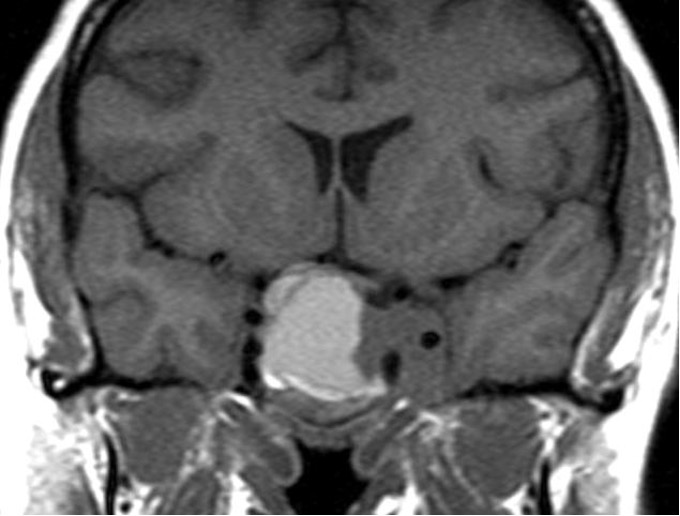

Figure 14. Coronal non-contrast image showing hemorrhage into an existing pituitary macroadenoma. The area of high signal represents the recent hemorrhage. There is a component of the tumor extending into the left cavernous sinus which does not show hemorrhage. The suprasellar extension is compressing the chiasm particularly on the right side.